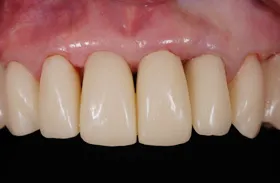

他院で「歯槽膿漏は治らない」と言われ、当院にご来院されました。歯が乱ぐいのため、歯並びもよくしたい、下は歯を既に失っているので噛めるようにもなりたい、またコーラスをされていて人前で口をあけることが多いので、できるだけ見た目を意識した治療をしてほしいとのご要望でした。

■治療(仮歯装着)後

■治療前